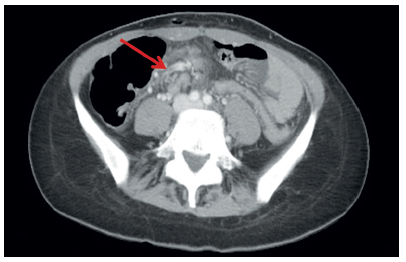

En el Servicio de Urgencias se solicitó una ecografía abdominal, en la cual se observó una lesión quística de 2 cm de diámetro correspondiente a un quiste del uraco e ileítis. Tras dichos hallazgos, la paciente ingresó a cargo del Servicio del Aparato Digestivo donde, dada la ausencia de mejoría del cuadro clínico, se ordenó una tomografía computarizada (TC) de abdomen y pelvis. En la misma, se identificaron cambios inflamatorios de la grasa mesentérica, y la raíz vascular del mesenterio se encontró rodeada por un manguito de tejido, correspondiente a una brida, además del tronco arterial común del que nacen la arteria gástrica izquierda, la hepática y la mesentérica superior, y la vena mesentérica superior que drena en la vena porta izquierda, conformando el signo del remolino (whirlpool sign) 4, y un probable quiste de uraco de 18 mm de diámetro (figuras 1 y 2).

Figura 1. Se observan los vasos arteriales arremolinados alrededor de la base del pedículo mesentérico. Este es el signo del remolino, visible en la tomografía computarizada cuando la malrotación intestinal se asocia con vólvulo del intestino delgado.